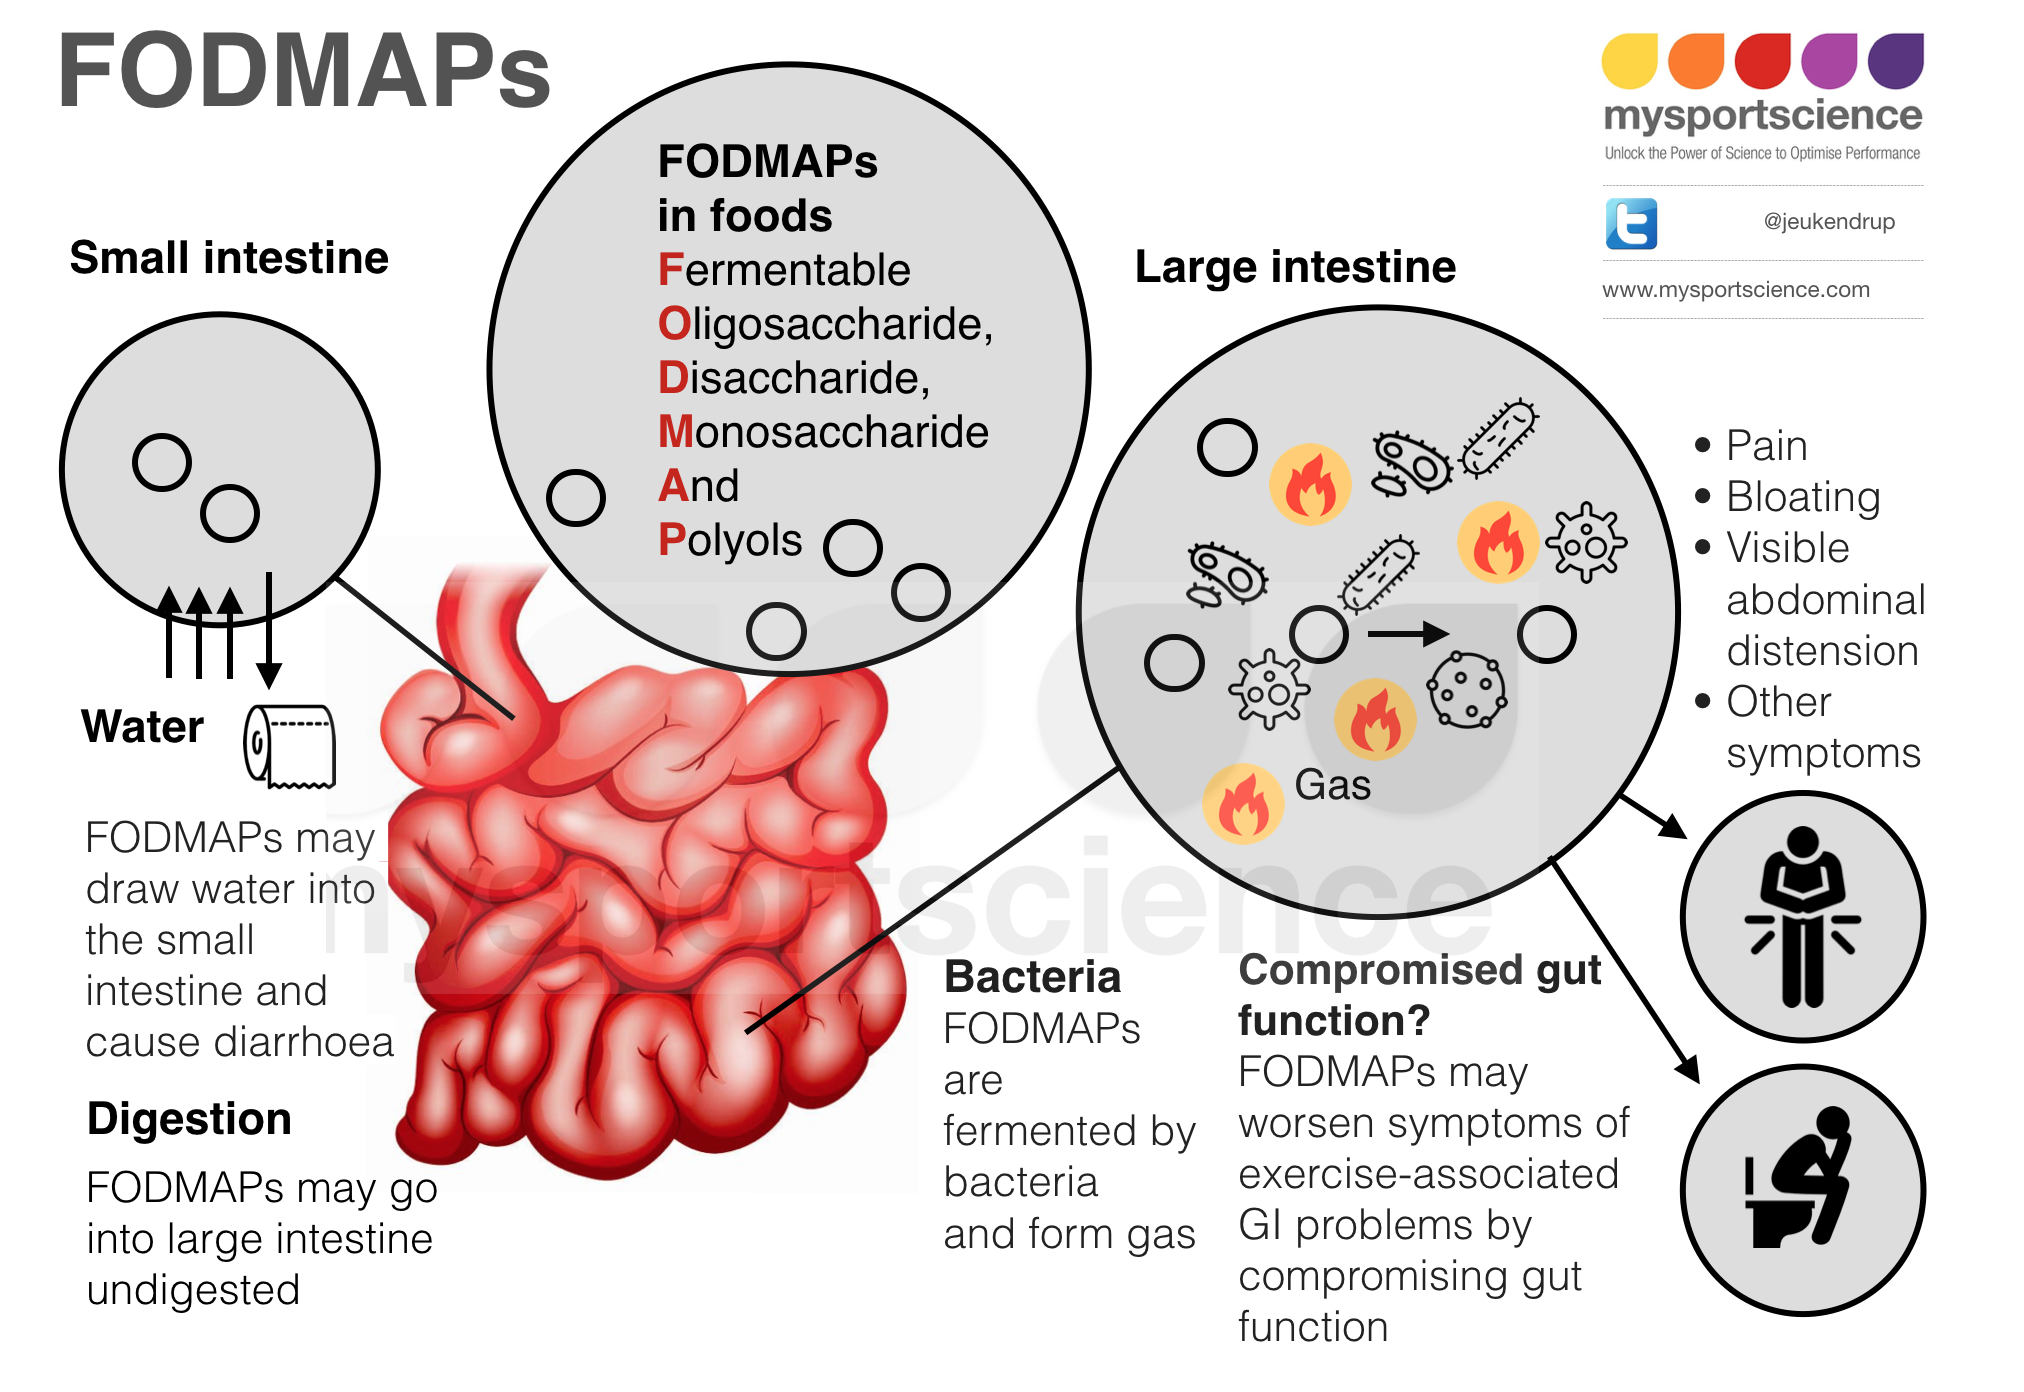

Recientemente la restricción en ciertos alimentos o por el contrario la ingesta de algunos se ha puesto de moda, (alimentos sin gluten, alimentos orgánicos, etc) lo cierto es que desde el punto de vista científico, ninguna de estas restricciones ha mostrado tener un efecto positivo en la salud. Sin embargo la dieta baja en FODMAPS, se ha puesto en el radar de los gastroenterólogos para ayudar en el tratamiento de los trastornos funcionales gastrointestinales.

¿Que es la dieta baja en FODMPAS? es un acrónimo en ingles

F: Fermentable

O: Oligosacáridos

D: Discáridos

M: Monosacáridos

A: And

P: Polioles

¿Para qué enfermedades es útil esta dieta?, en general se recomienda para personas con síndrome de intestino irritable, dolor abdominal crónico funcional o dispepsia funcional. Es importante mencionar que no es necesaria la suspensión de todos los alimentos que pudieran estar incluidos, si no que la dieta se ajusta de acuerdo al paciente.